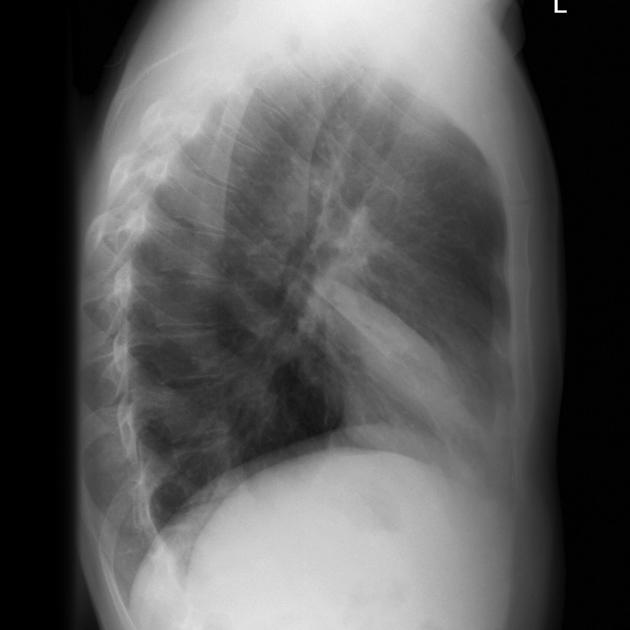

Describe the abnormality demonstrated.

Loss of definition of the left cardiac border due to opacification in the left upper lobe and elevation of the right hemidiaphragm, in keeping with a left upper lobe collapse.